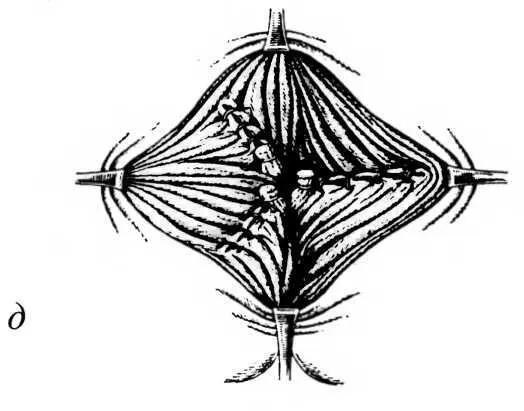

| Рис. 21. Геморроидэктомия с полным восстановлением слизистой оболочки. а - отсечение узла над зажимом Бильрота до сосудистой ножки; б - прошивание ножки узла; в, г - ушивание раны стенки заднепроходного канала наглухо; д - вид ран канала после операции |